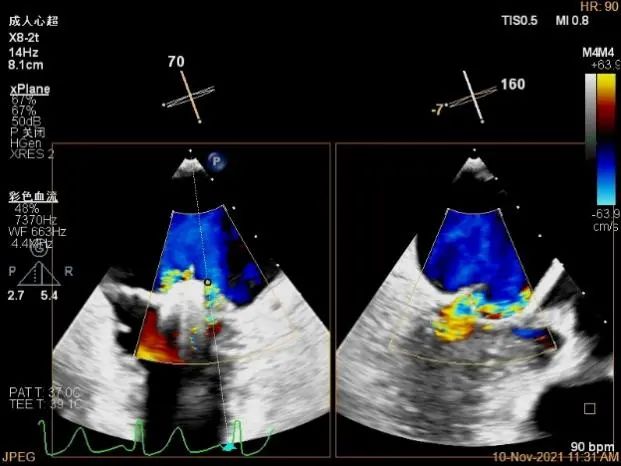

2D视图下进第二个夹子

将第二个夹子置于第一个夹子外侧并调整Orientation

成功抓捕外侧残余脱垂区域瓣叶

第二个夹子外侧残余小束分流,宽3.7mm

3D视图两个夹子近似并排排列,第二个夹子外侧小残余脱垂,瓣叶裂孔已不明显

肺静脉血流频谱恢复正向

肺静脉血流频谱完全正向

二尖瓣瓣口平均跨瓣压差:5mmHg